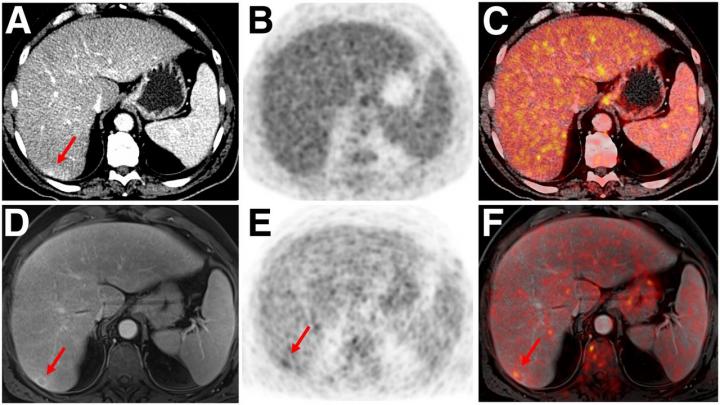

image: Indeterminate lesion on PET/CT classified by PET/MRI for 53-y-old man with lung cancer. Contrast-enhanced CT (A), PET (B), and fused 18F-FDG PET/CT (C) images are displayed in comparison with contrast-enhanced T1-weighted MRI (D), PET, and fused 18F-FDG PET/MRI (F) images. In CT (A), hyperdense, subcentimeter liver lesion (arrows) in segment VII is suggestive of transient hepatic attenuation difference or small hemangioma. As malignancy cannot be excluded, it needs further investigation. On PET/MRI, lesion is clearly classified as metastasis because of contrast enhancement and tracer uptake due to later acquisition time point. Follow-up CT confirmed diagnosis after 78 d.

Images created by Ole Martin, University Dusseldorf, Medical Faculty and Benedikt Schaarschmidt, University Hospital Essen.